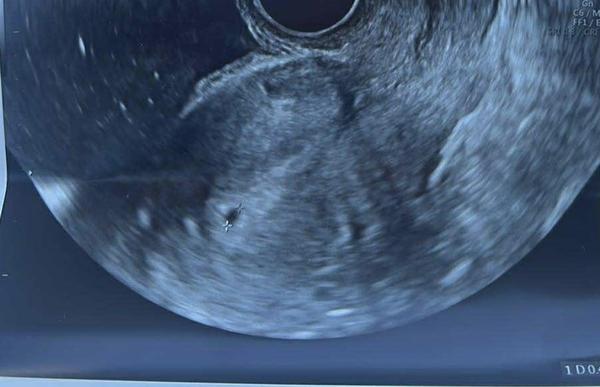

7.1. Videl doktor toto

@anonym_afd62e mas to ako ja. A o týždeň si bola na kontrolu a ako bolo vidieť ?

@olivia20 videl už aj zltkovy vak a zárodok plodu zatiaľ bez akcie srdca